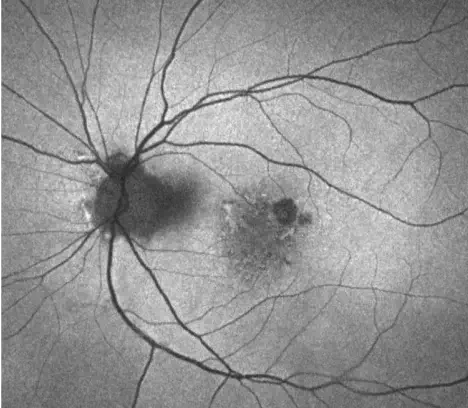

INDICATION

IZERVAY™ (avacincaptad pegol intravitreal solution) is indicated for the treatment of geographic atrophy (GA) secondary to age-related macular degeneration (AMD)